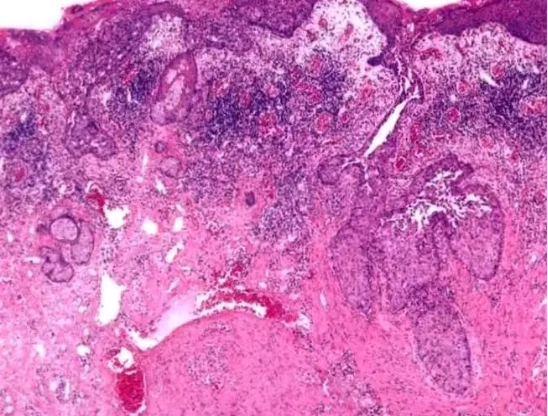

第四,蛛網膜囊腫。很多人認為這是一種非常嚴重的疾病。認為是囊腫泡裡面的腫塊和化膿性物質,有些人甚至把囊腫錯認為腫瘤,實際上,蛛網膜囊腫是先天性的良性病變,是發育異常下蛛網膜異常分裂所導致的,在人體內並沒有明顯的症狀,只要進行定期複查和觀察就可以了,不需要進行後續的手術治療和藥物治療。